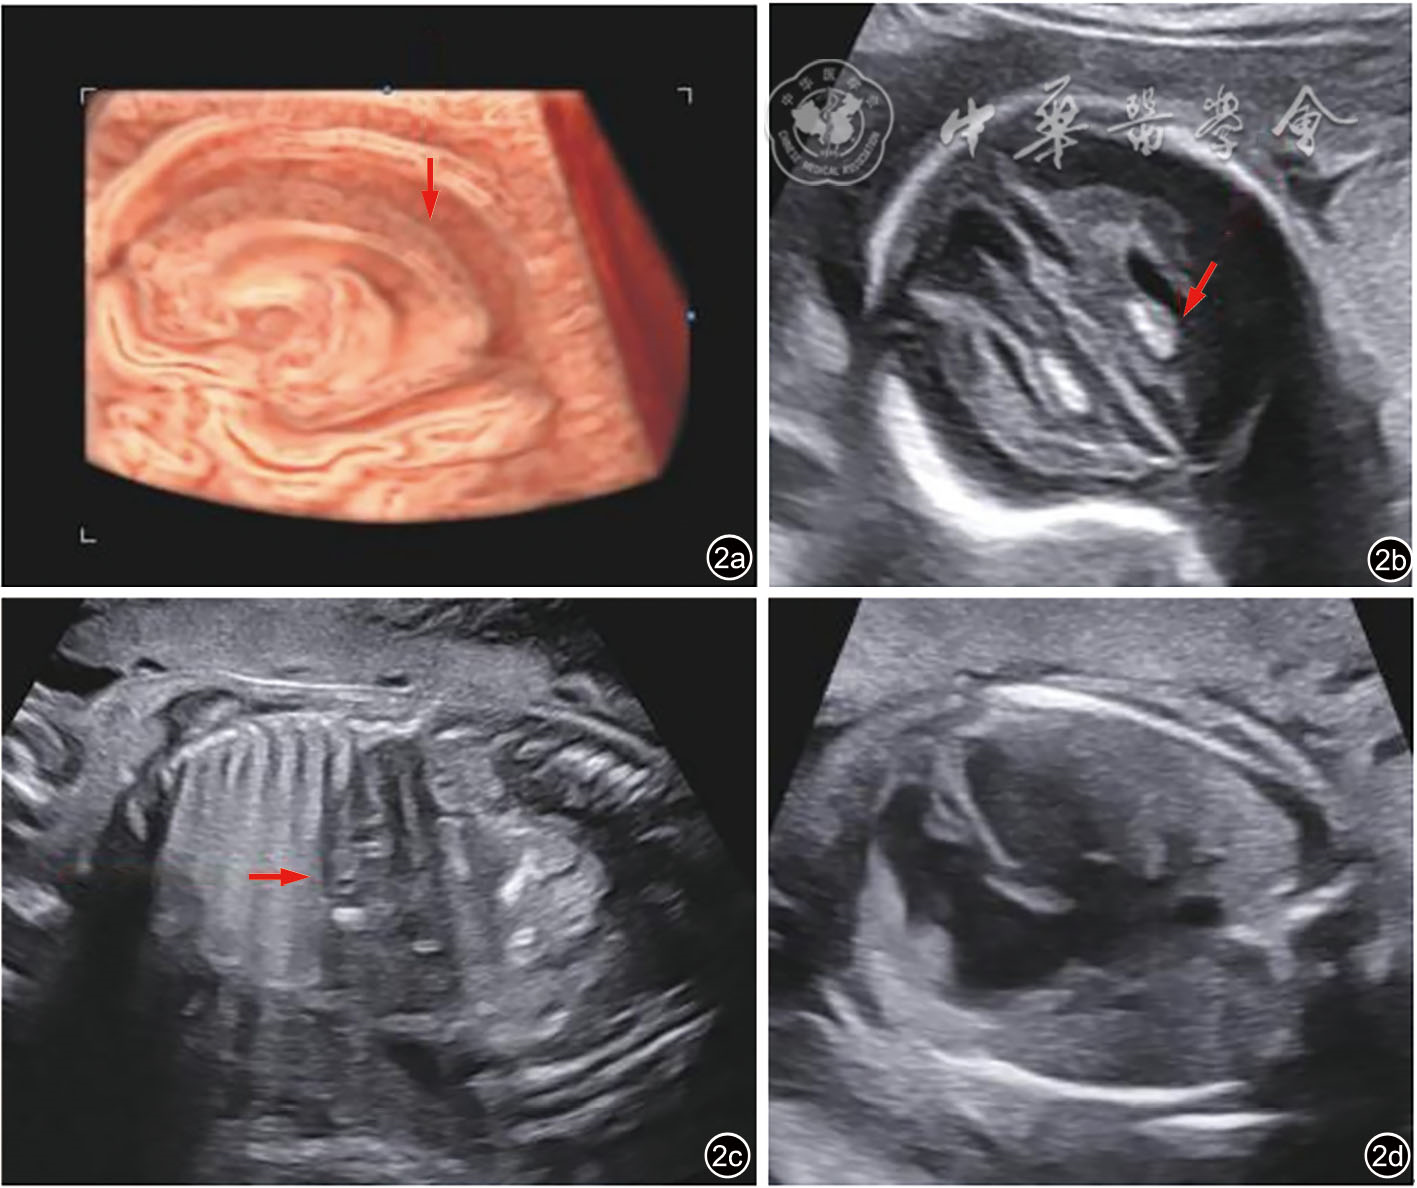

孕妇29岁,孕2产0,孕12周超声检查提示胎儿颈项透明层厚度正常,唐氏综合征筛查及无创胎儿染色体非整倍体检测均为低风险,孕23+1周Ⅲ级超声检查提示胎儿发育异常:胎儿大脑实质板下带与中间带明显分层(图1a),颅内、肝内多发强回声(图1b、1c),肝脾大(肝长径为4.62 cm,对应孕周上限为3.62 cm;脾肋下约0.8 cm),肠道回声增强(图1d),提示宫内感染可能;胎儿体质量数值位于第3百分位数,脐动脉阻力增高、大脑中动脉阻力降低,脑胎盘比<1,羊水少,符合胎儿生长受限(fetal growth restriction,FGR)的诊断。夫妻既往身体均健康,非近亲结婚,否认孕前、孕期毒物与放射线接触史,否认家族遗传病史,孕前致畸五项(风疹病毒、弓形虫、巨细胞病毒、单纯疱疹病毒1型和2型)均阴性。经遗传咨询,行羊膜腔穿刺,结果提示羊水染色体核型及染色体微阵列分析均未见异常,风疹病毒及巨细胞病毒IgM定量检测均为阴性。孕25+3周复查超声提示:胎儿大脑实质板下带与中间带明显分层(图2a),颅内、肝内多发强回声(图2b、2c),肝脾大(肝长径4.29 cm,对应孕周上限为3.94 cm;脾肋下约1.34 cm),心胸面积比增大(图2d)。胎儿体质量数值位于第0.45百分位数,脐动脉阻力增高、大脑中动脉阻力降低,脑胎盘比<1。孕妇加查羊水家系全外显子组测序(whole exome sequencing,WES),结果提示:在RNASEH2A基因上检出2个与胎儿表型相关的意义不明变异,相关疾病为:Aicardi-Goutieres综合征4型,常染色体隐性遗传。经过Sanger测序验证,分别来源于父母。超声已明确胎儿为脑皮质发育畸形(malformations of cortical development,MCD),孕周未满28周,未行头颅MRI检查。由于胎儿并未出生,很多功能学表型无法从宫内抓取,很多表型及影像学特征需要在胎儿出生后体现,如神经系统异常所致的智力残疾,均需要胎儿出生后才能得以验证。但根据现有的影像学结果,胎儿诊断为MCD明确,预后不良可能性大,经过多学科讨论,孕妇夫妻知情选择终止妊娠。本病例报道通过医院伦理委员会批准(KYYS-2025-040)。

图2 孕25+3RNASEH2A基因复合杂合变异胎儿超声图像。图a示胎儿大脑实质板下带与中间带明显分层,图b示颅内多发强回声,图c示肝内多发强回声,图d示心胸面积比增大(0.36)